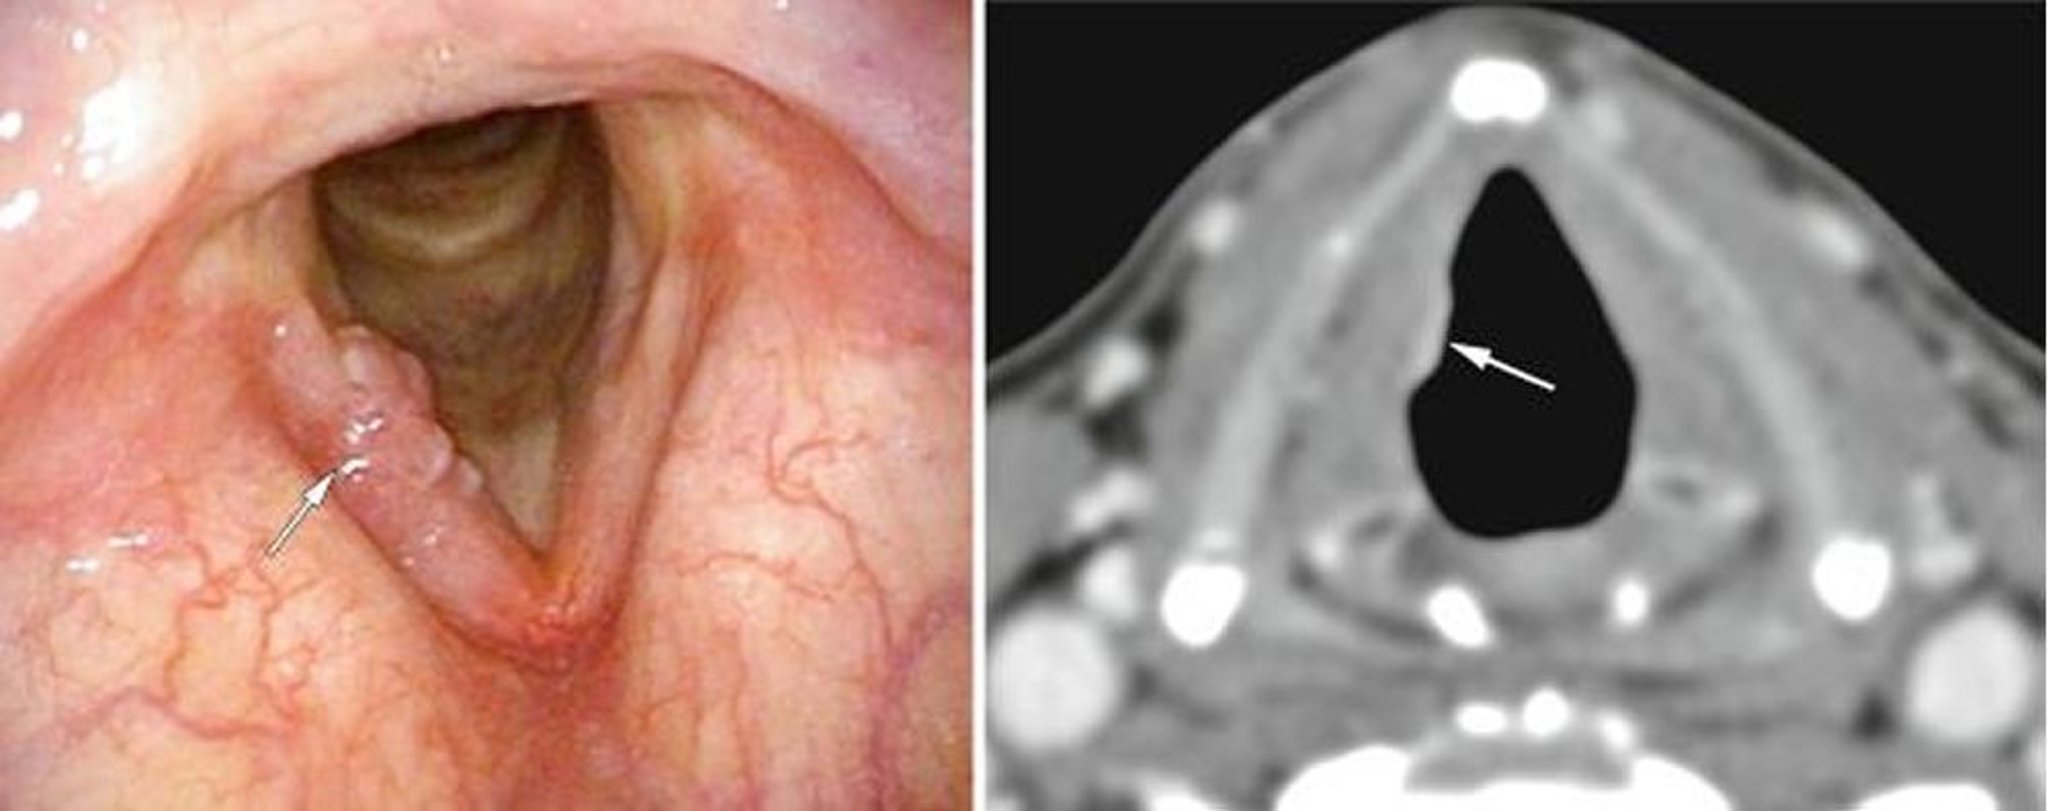

Câncer laríngeo precoce

Esse paciente teve câncer de laringe glótico em estádio inicial, aqui visível em uma das pregas vocais à endoscopia (imagem à esquerda, flecha branca) como excrescências, e na TC (imagem à direita, flecha branca) como uma densidade anormal de tecidos moles.